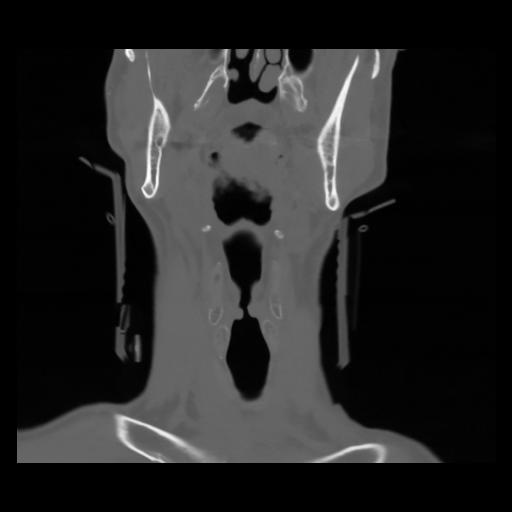

13 P.BLANDAS,,Coronal,2.000,P.BLANDAS,Coronal,